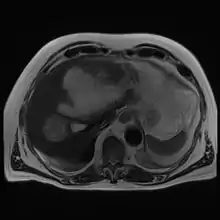

| Gross pathology of liver containing amoebic abscess | |